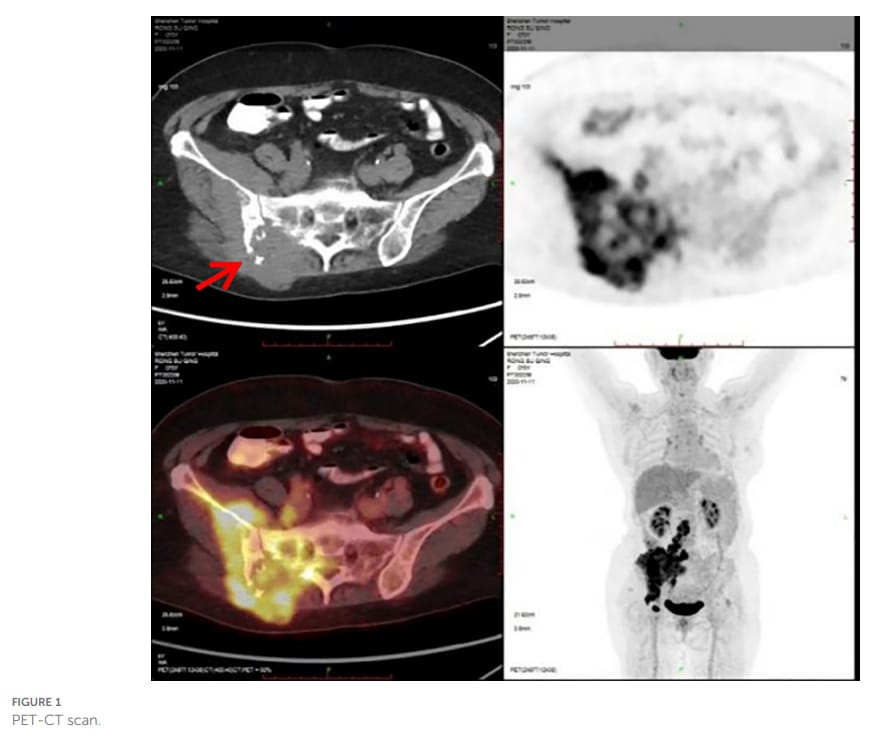

患者为一名76岁女性,因右侧臀部进行性增大的疼痛性肿块就诊。经过一系列影像学检查,包括PET-CT,结果显示其右侧臀部存在一个巨大的软组织肿块(最大截面达11.8 cm),并已发生广泛的局部侵犯和多处远处转移,包括骨、肌肉、淋巴结及双肺。这是一个典型的晚期恶性肿瘤表现。